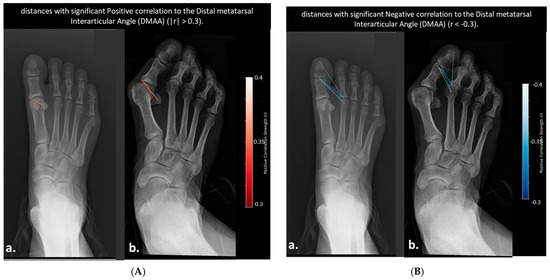

- Color Scale: The gradient ranges from dark blue (−0.6) to dark red (0.6), indicating the strength and direction of correlation (negative to positive).

- Correlation Coefficients: Values are color-coded, with significant correlations (p < 0.05) highlighted. Notable ranges include r > 0.4 for HVA and IMA, and r > 0.3 for DMAA and HIA.

- Annotations: Specific distances (e.g., “2nd metatarsal head to proximal phalanx head,” “Medial sesamoid to proximal phalanx base”) are labeled to reflect anatomical relationships.

- Distances Correlated with Distal Metatarsal Articular Angle (DMAA)